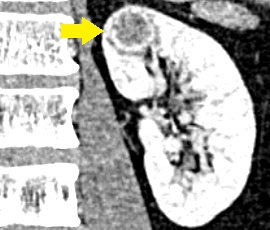

CT画像